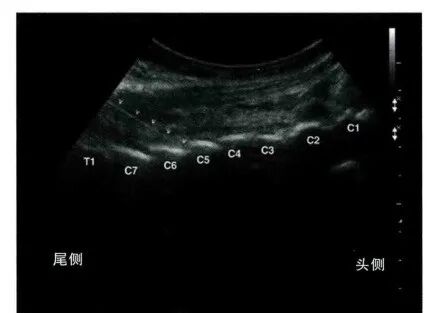

采用平面内技术,在选定的穿刺点,以长3.5英寸带芯穿刺针在超声探头的下方以小关节为靶点从尾侧向头端方向进针( 图9和图10 )。

图9 / 超声引导下颈椎小关节内阻滞